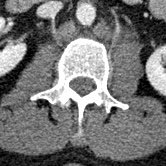

IM-0005-0083 L-spine.jpgIM-0003-0038 L3.jpgIM-0003-0031 L2.jpg

The fly-through doesn’t show the spinal injury very well, so here are some 2-D sections. The left panel is a section of my lumbar spine viewed from my left side; note the obviously smashed L3 vertebra. The middle panel is a top-view slide of L3, and the right panel is healthy L2 (the vertebra immediately above) for comparison.